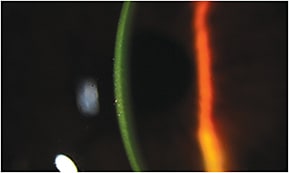

Due to the presence of epithelial tight junctions, achieving desirable stromal riboflavin concentration was perceived as challenging because of the macromolecular and hydrophilic characteristics of riboflavin-Dextran; therefore, it was regarded as essential by the Dresden Protocol to first remove epithelium prior to CXL treatment. Typically, when performing the Dresden Protocol at our center (Cornea and Laser Eye Institute-Hersh Vision Group), epithelial debridement is conducted over the central 9mm zone after administration of topical anesthesia. Over the next 30 minutes following epithelial removal, topical riboflavin is instilled every two minutes. At the conclusion of this loading phase, stromal riboflavin saturation is confirmed via slit lamp examination (Figure 1).

Figure 1. Anterior chamber evidence of corneal riboflavin saturation in an epi-off CXL case.